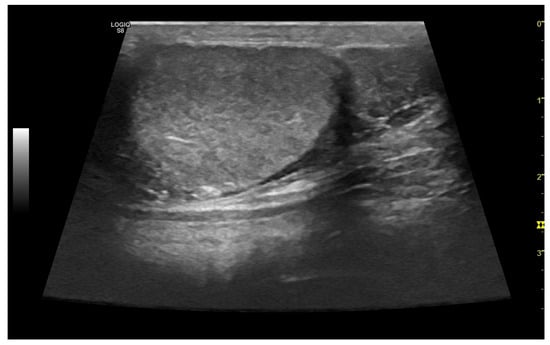

3. Grey-Scale Ultrasonography

3.3. Normal Findings

3.4. Abnormal Findings

3.4.1. Intratesticular Diseases